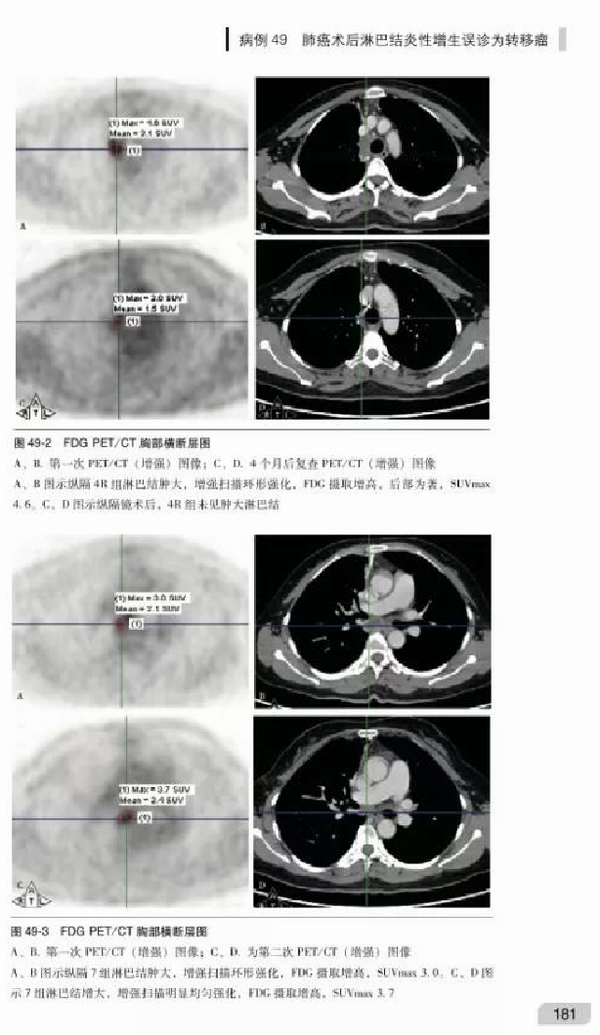

1. 延续第1版的优点,强调病例资料的完整和可追溯性、充分展示PET/CT与其他影像图片、突出诊断思路的透彻分析和精准的点评;

3. 新增难度系数较大的精彩病例,尤其是肿瘤以及容易与肿瘤混淆的良性病变的疑难病例;

5. 病例总数增加至122例,肿瘤病例75例,常需与肿瘤鉴别诊断的其他疾病47例。